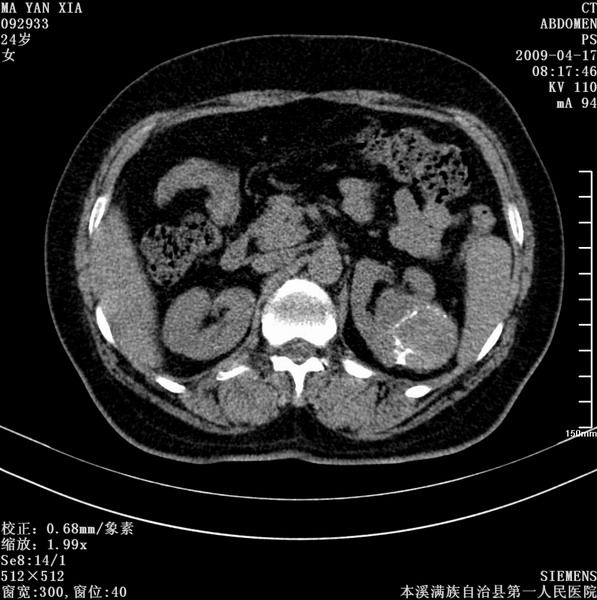

标题: CT19443:肾脏肿瘤两个区强化不一样。 [打印本页]

标题: CT19443:肾脏肿瘤两个区强化不一样。

女,51岁,体检时发现肾脏占位,建议ct增强。无任何自觉症状。

典型的不均匀强化,左肾癌